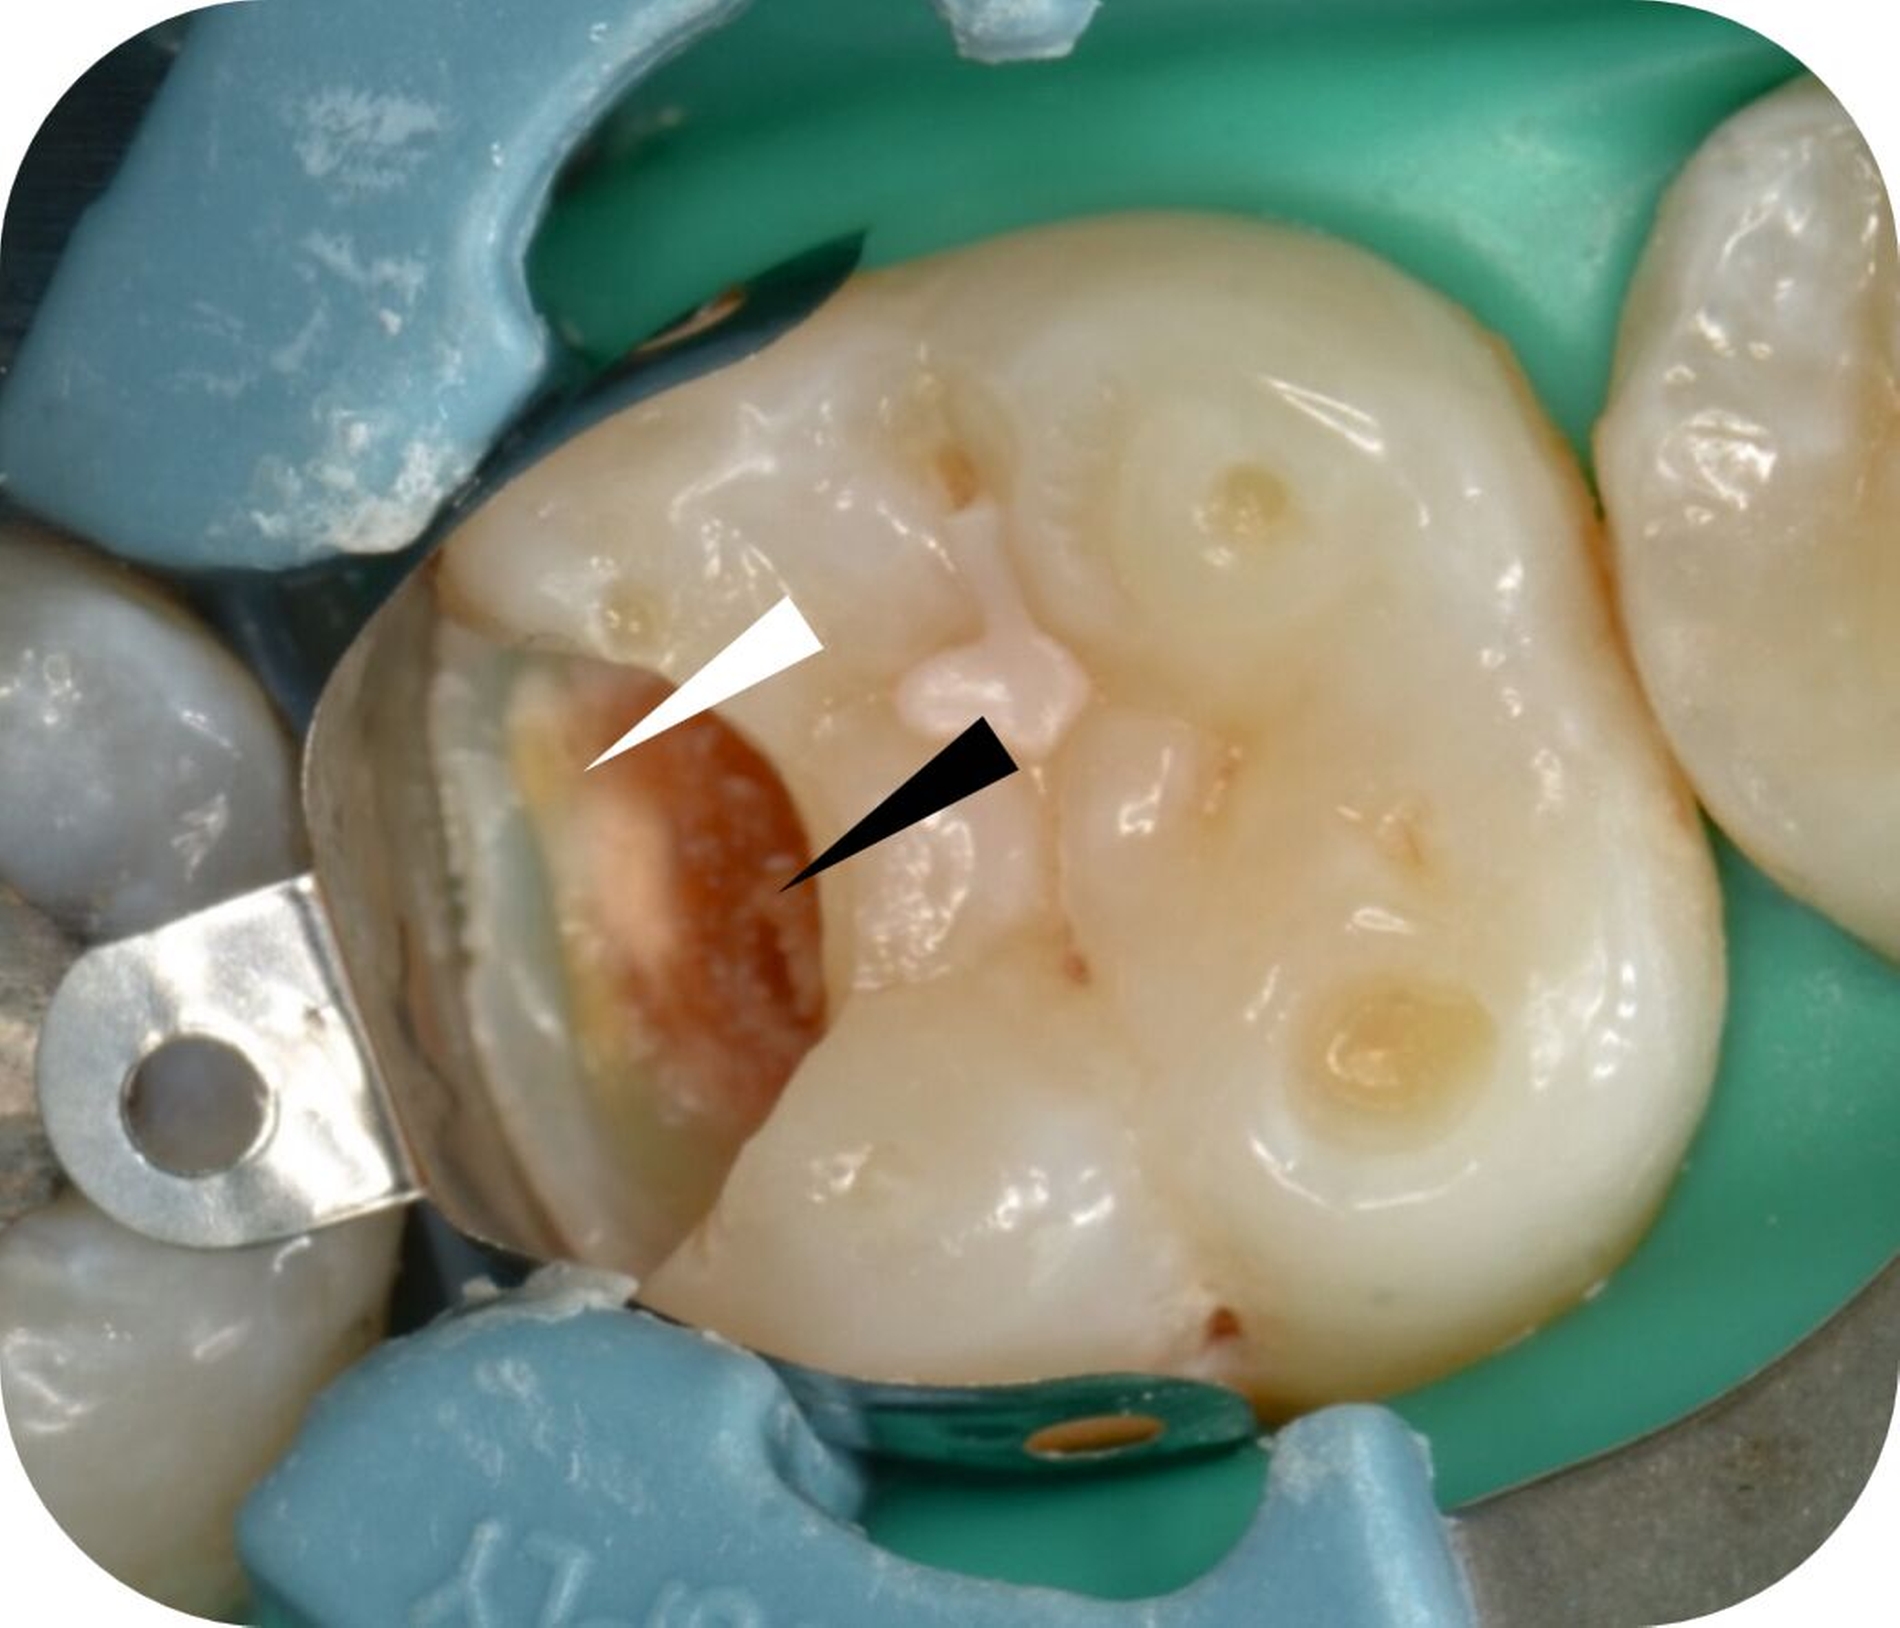

Bei der Definition des Endpunkts der selektiven Kariesentfernung gibt es Unterschiede, die je nach Arbeitsgruppe variieren. Die hierzulande gängige Beschreibung definiert die non-selektive Kariesentfernung als Entfernung von erweichtem und festem kariös verändertem Dentin sowohl in peripheren als auch in zentralen beziehungsweise pulpanahen Bereichen der Kavität (Abbildung 1). Als Endpunkt gilt dabei „hartes Dentin“ [Widbiller et al., 2022; Schwendicke/Göstemeyer, 2016]. Im Unterschied dazu verbleibt bei der selektiven Kariesentfernung pulpanah festes (mit Handexkavator schneidbares) oder weiches Dentin (Abbildungen 1B distal und Abb. 3 schwarzer Pfeil). Peripher wird das Dentin bis zur Sondenhärte entfernt (Abbildung 3, weißer Pfeil), bevor die Kavität anschließend direkt mit einer definitiven adhäsiven Restauration versorgt wird (Abbildung 4) [Widbiller et al., 2022].

Bei der selektiven Kariesentfernung sind verschiedene Substrate für die adhäsive Anbindung vorhanden (Abbildungen 3 und 5). Neben Zahnschmelz treten regelmäßig unverändertes Dentin, sklerotisches Dentin, kariös verändertes Dentin (caries-affected) sowie eventuell pulpanahes infiziertes kariöses Dentin (caries-infected) nebeneinander auf (Abbildung 5) [Isolan et al., 2018]. Der adhäsive Verbund ist an kariös verändertem und insbesondere erweichtem Dentin beeinträchtigt [Lennon et al., 2023]. Im Mikrozugfestigkeitsversuch erzielten Lennon et al. am kariös veränderten Dentin bessere Ergebnisse mit Universaladhäsiven im Self-etch-Modus verglichen mit Etch-and-Rinse-Adhäsiven.

Weitere Untersuchungen bestätigten, dass unverändertes Dentin eine deutlich bessere Haftung zu Adhäsivsystemen aufweist als sklerotisches, kariös verändertes oder infiziertes Dentin [Hass et al., 2019; Nakajima et al., 1995]. Da klinisch jedoch häufig verschiedene Dentinzonen gleichzeitig auftreten (Abbildungen 3 und 4), bleibt die Gesamthaftung ausreichend, sofern eine ausreichende Fläche nicht kariös veränderter Zahnhartsubstanz im peripheren Bereich der Kavität (periphere Versiegelungszone) vorhanden ist. Die Haftung kann dabei regional eingeschränkt sein [Innes et al., 2016]. Die Menge des belassenen, weichen kariösen Dentins im Kavitäten zentrum könnte klinisch relevant sein. Bei größeren Mengen zurückgelassenen weichen Dentins kann durch Feuchtigkeitsverlust nach dem Verschluss eine Schrumpfung entstehen [Bjørndal, 2018]. Daraus resultierende Hohlräume unter der Restauration erzeugen Spannungsspitzen im Randbereich, die den ohnehin beanspruchten adhäsiven Verbund zusätzlich belasten und den Therapieerfolg beeinträchtigen können. Diese potenziellen Nachteile lassen sich jedoch durch eine defektorientierte, minimalinvasive Präparation mit reduzierter Kavitätengröße kompensieren, selbst wenn der Anteil veränderten Dentins am Volumen der Kavität am größten ist. Insgesamt ist die Wirkung der Schmelz- und Dentinhaftung auch in Fällen mit reduzierter Haftung im kariös veränderten Dentin klinisch ausreichend, um dauerhaft stabile adhäsive Restaurationen anzufertigen.